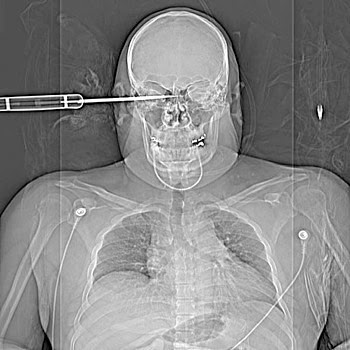

Asta-i îngrozitoare: un accident cu un pistol de cuie… Mă întreb dacă respectivul a supravieţuit.

Un sergent din armata SUA, înjunghiat în cap (faţă) pe străzile din Baghdad.

cel cu cuiele a supravietuit. daca o fi tot ala. am vazut mai demult ceva despre el. din fericire nu-i atinsese nimic vital… noroc chior